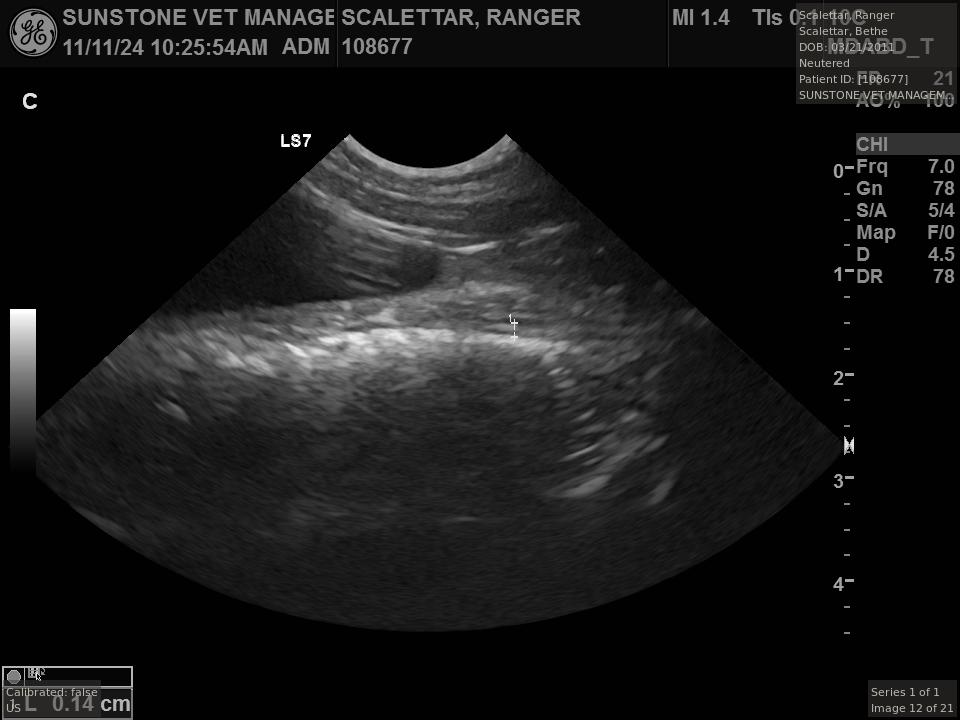

The veterinarian generated a series of images showing different organs and substructures by

changing the position and orientation of the ultrasound transducer. The images were collected

in a defined order, which is repeated from patient to patient, ensuring that nothing is missed. In

Ranger's case, the sonographer collected about twenty images during an examination that

lasted about fifteen minutes.

The sonographer stated that Ranger's ultrasound images were largely normal for an older cat. In particular, they show changes in the kidneys that are commonly noted in geriatric cats and that reflect a risk for the development of chronic kidney disease. However, the images did not show any significant abnormalities in Ranger's stomach, intestines, and associated lymph nodes. Nonetheless, the results did not rule out recurrence of Ranger's small cell lymphoma.